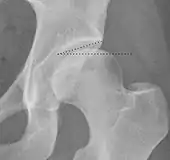

- (A) Hilgenreiner line, connects the inferior tips of the iliac bones,[4] at the triradiate cartilage. This line is used to measure the acetabular angle and as a reference for Perkin line.

- (B) Perkin line is perpendicular to Hilgenreiner line, touching the lateral margin of the acetabular roof.[5] This leads to four quadrants and a normal femoral head has to be located in the inferomedial quadrant. We can measure the lateral displacement of the femoral head with regard to the Perkin line by dividing the width of the head that crosses the Perkin line by the diameter of the head. The value for patients under 3 years must be 0 and in older children this ranges from 0 to 22%.

- (C) Shenton line is a continuous arc drawn from the inner edge of the femoral neck to the superior margin of the obturator foramen. In children over about 3 to 4 years of age, this line should be smooth and undisrupted, otherwise it may indicate a fracture or hip dysplasia.[6] However, in infants this line can be unreliable as it depends on the rotation of the hip when the image is taken.[7]

- (D) The acetabular index measures the acetabular roof slope. It is the most useful measure of acetabular dysplasia until 6 years of age. It is formed between Hilgenreiner line and the acetabular roof. In newborns, values of in males and in females are considered normal. It normally decreases with age:

- (E) The medial articular joint space is measured between the medial border of the femoral head or neck (when epiphysis is not ossified) and the acetabular platform. Normal values range between 5 and 12 mm. Differences greater than 1.5 mm between the two sides are considered abnormal.

- Reimer's migration index (MI), also called the femoral extrusion index,[3] is calculated if hip dysplasia is detected. It can be used to indicate hip dislocation. It is the horizontal distance (parallel to the Hilgenreiner Line) between the Perkin line and the lateral border of the ossification center of the femoral head, divided by the horizontal width of the ossification center. The migration index is normally less than 33% by most sources,[9] but 25% and 30% has also been suggested.[10]